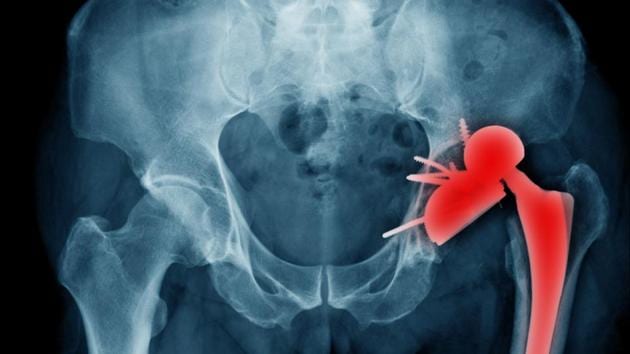

The researchers showed that spinal deformity was a significant risk factor for dislocation and subsequent revision surgery. In a hip replacement, an artificial joint comprising a ball and socket is implanted to replace the natural ball and socket in the pelvis, enabling movement that is typical of the hip joint.

“Dislocation is a common reason for a total hip replacement to fail, and when it happens, sufferers can experience significant pain and require another surgery to fix the problem,” said lead author Jonathan Vigdorchik, assistant professor at the New York University School of Medicine.